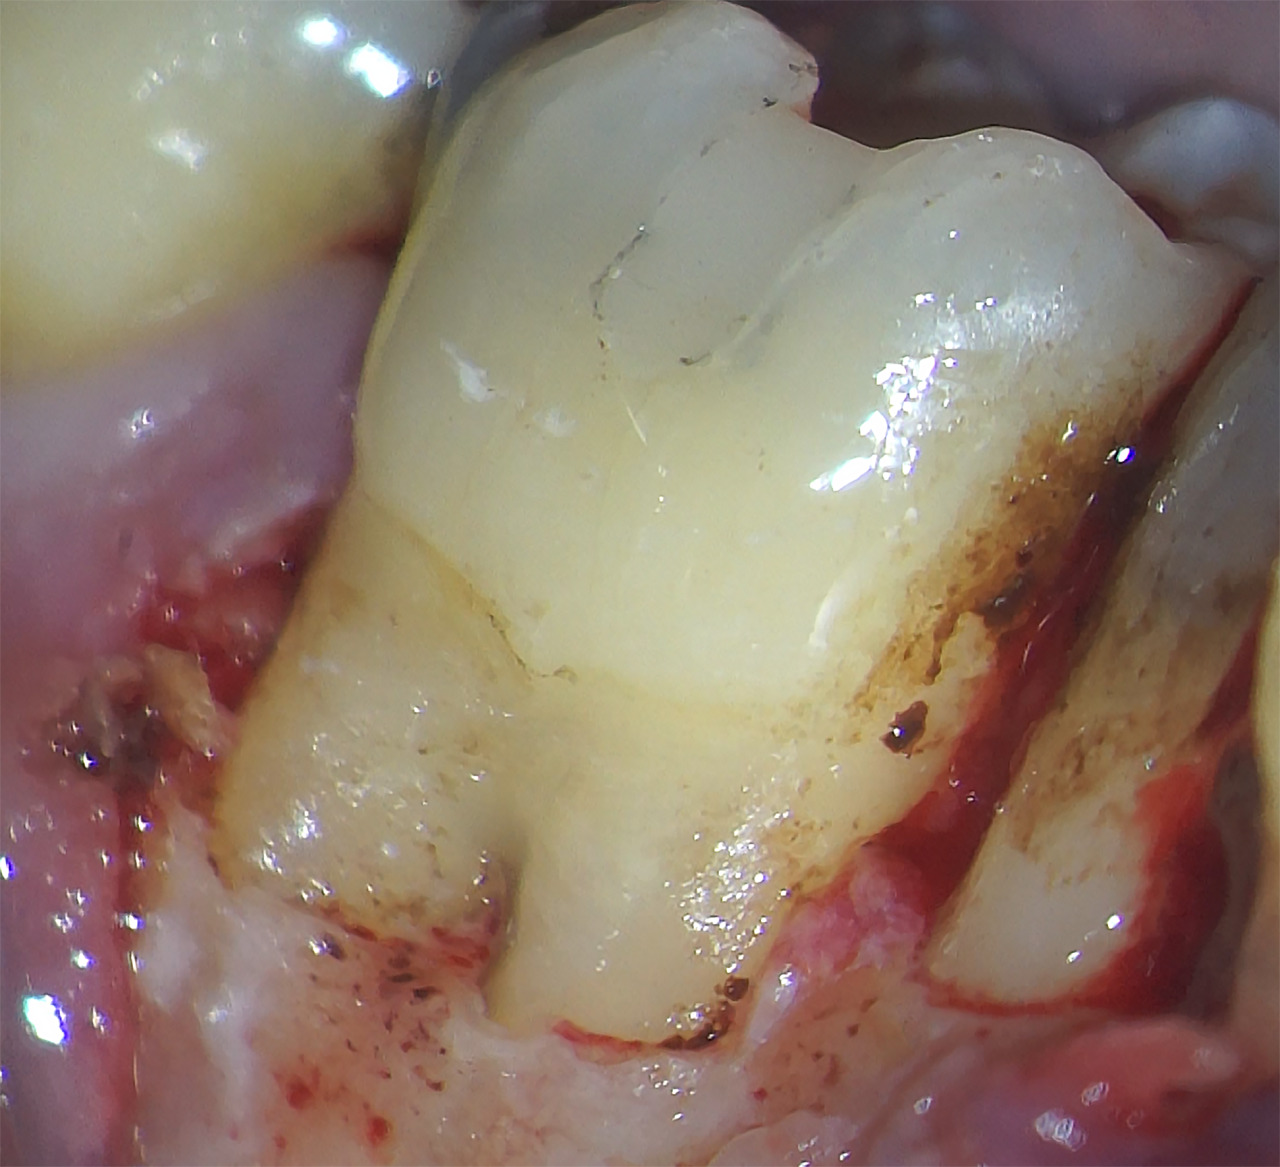

Dans ce troisième temps, l’objectif est d’atteindre la lésion de résorption afin de la cureter correctement, convenablement et entièrement. Pour ce faire, un lambeau de petite étendue est levé avec une incision de décharge en mésial et une incision en circulaire sur la dent 36 uniquement. Le lambeau est récliné, la lésion est très vite mise en évidence (Fig.15).

Elle est alors nettoyée avec un insert ultra-sonore diamanté, courbé, de chirurgie endodontique (insert RD25, Woodpecker, Chine) (Fig.16). Le curetage est minutieux et permet, à un moment donné, de mettre en évidence la gutta percha que l’on reconnaît au sein du canal.

La cavité est alors séchée puis obturée avec un composite fluide, collé (Fig.17). Le choix du matériau pour cette étape reste également un sujet de discussion. Aurait-il fallu préférer un ciment au verre ionomère ? ou directement du MTA ? Ce dernier présente l’inconvénient d’une faible résistance au Wash out, ce qui est préjudiciable au moins le temps de la cicatrisation de première intention. Une fois l’obturation terminée, la gencive est remise en place et suturée avec un fil de suture en Prolène 6-0 (Atramat, Brésil).

Fig.15 : Vue de la lésion de résorption sur la racine mésiale de la dent, après avoir décollé le lambeau de pleine épaisseur.

Fig.16 : Préparation de la cavité de résorption à l’aide d’un insert ultra-sonore de chirurgie endodontique.